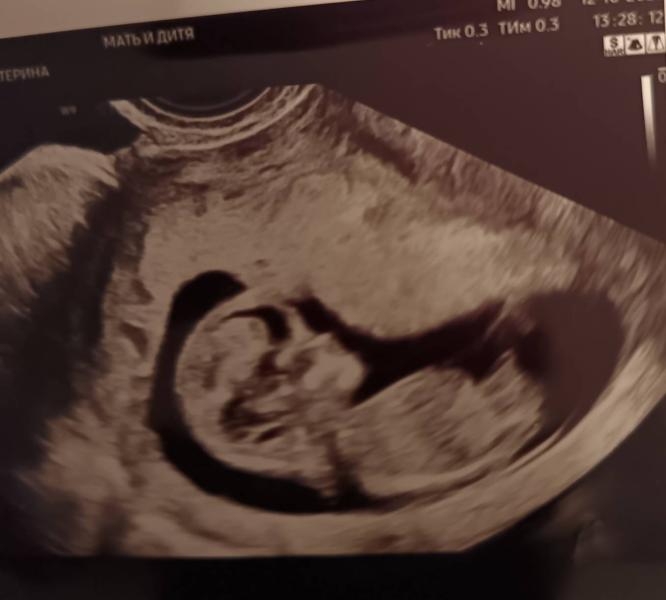

Сегодня был 1й скрининг, по УЗИ все хорошо, кровь должна позже прийти. Посмотрим какие риски.

#беременность40 + #1йскрининг

Сказали какой пол малыша, смотрю на узи, похоже на девочку по половому бугорку

@rinadjie, мне видно) а им не видно) странный узист